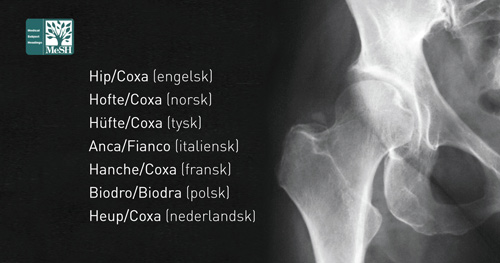

Siden hver MeSH har sitt id-nummer, åpner det for mange datatekniske bruksmuligheter. Parallellspråklighet vil ikke bare gjelde for norsk og engelsk, men også tysk, finsk, polsk, svensk, fransk, spansk, italiensk osv. Lurer du på hva et fransk medisinsk ord er på norsk, engelsk e.l., kan du finne ut det i basen. Det søkes å gjøre MeSH tilgjengelig som «linked data», og vi deler erfaring med finnene og svenskene i dette arbeidet. MeSH kan kobles til kodesystemer som ICD-10, ICPC-2, ATC osv., slik at begrepssystemene kan utfylle og berike hverandre (4). I samarbeid med den franske helseportalen CISMeF er norske oversettelser av MeSH og andre kodesystemer tatt inn i The European Health Terminology/Ontology Portal (EHTOP). Norske MeSH inkluderes nå i databasen SveMed+ for å forbedre gjenfinningen av litteratur for nordmenn, som faktisk utgjør to tredeler av brukerne.